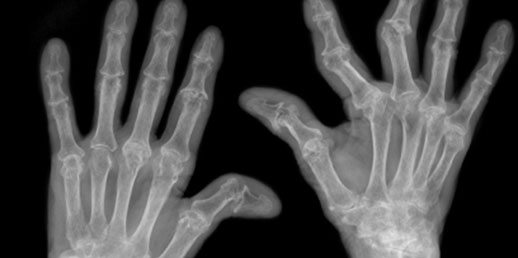

Astrazeneca har presenterat resultaten av en klinisk fas III-studie med läkemedelskandidaten fostamatinib mot reumatoid artrit. Studien, Oskira-1, hade två primära mål. Dels bedömning av tecken och symptom av reumatoid artrit enligt skalan ACR 20, som bygger på procentuell förbättring av symptom och bedömning enligt en röntgenologisk skala, mTSS, som mäter benerosion och minskning av ledspringan med hjälp av röntgen.

Däremot visade kandidaten ingen statistiskt signifikant skillnad i mTSS jämfört med placebo efter 24 veckor för någon av doseringarna.